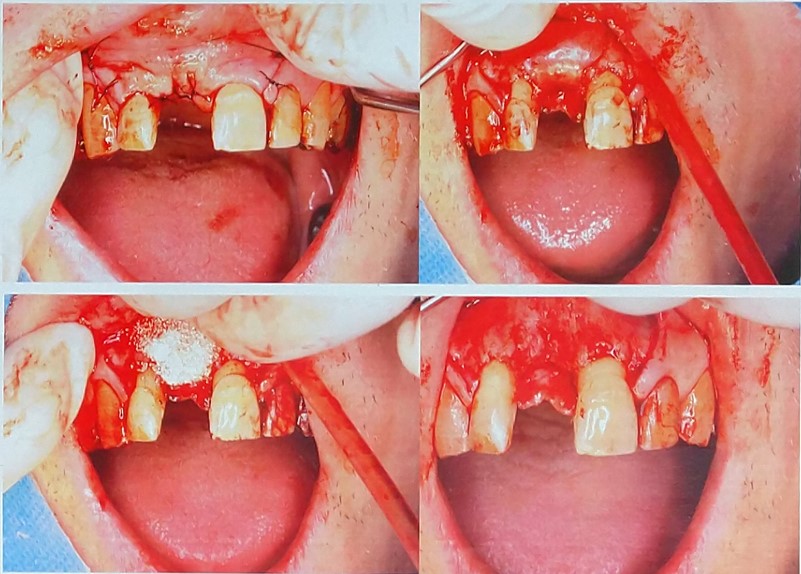

参考までに骨造成手術時の写真を添付します。

30〜60分程度と言われた手術が、自骨採取時にノミを強く打ち付け

空洞部が陥没、ボーンタックが空洞部に落ち込み、

なかなか取れず、先生が入れ替わり立ち代わり1時間近くかかって

やっと取れ、陥没部は封鎖して、自骨はまた別の場所から採取し、

結果、手術時間が2時間15分かかりました。

この間、切開部は暴露状態で、術後、尋常でないくらいに腫れ上がり、

正確にはこの術後から歯に触れるだけで痛みがずっと生じています。

健康な両隣の歯茎までも広範囲に切開したのか疑問に思いますが、

画像1骨造成.jpg